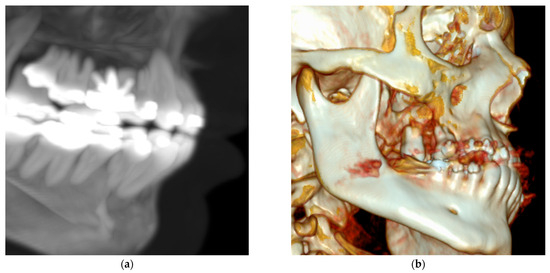

Background/Objectives: Tooth extraction is known to cause both bone loss and soft tissue collapse, changes that can complicate implant placement. While alveolar ridge preservation techniques have been proposed to limit these alterations, they often f...